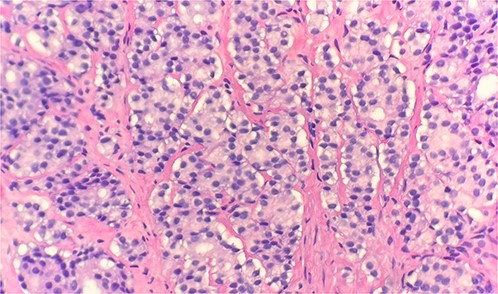

Specimen received in formalin and consists of multiple needle cores soft tissue measuring up to 1.2 × 0.1 cm. Microscopic examination reveals sheet of tumor cells forming nest or trabecular invasive pattern (Fig. 1). Tumor cell are immunopositive for PSAP (Fig. 2) and Alpha methyacyl CoA racemase (p504s) (Fig. 3), and focally positive for CDX2 (Fig. 4). Negative staining for CK7, TTF1 and Napsin A make lung primary less likely. Negative staining for CK20 speaks against lower GI tract primary. Combined with morphological features, this immunoprofile supports the diagnosis of metastatic adenocarcinoma with patient’s known history of prostate primary.

Microscopic examination reveals sheets of tumor cells with invasive growth pattern (H&E stain 40×).